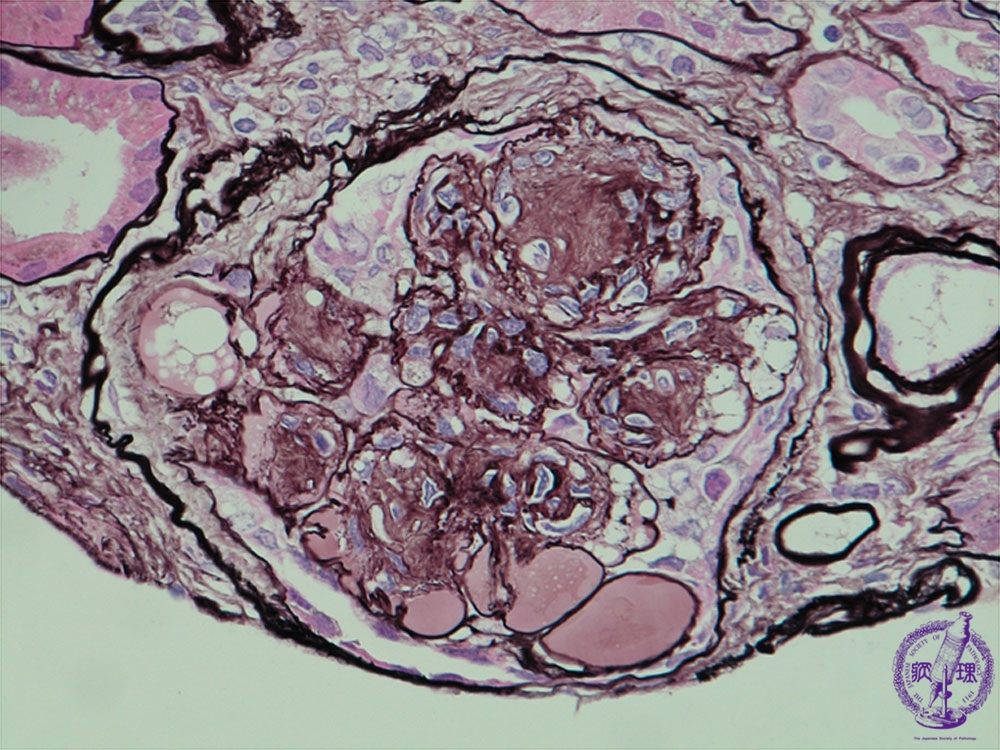

- (7)Diabetic nephropathy

Microscopic findings (PAM, high power): A nodular component is demonstrated by accumulation of mesangial matrix (yellow dotted line) whereas an exudative component is established by exudates within capillary loop vessel walls (yellow arrow).